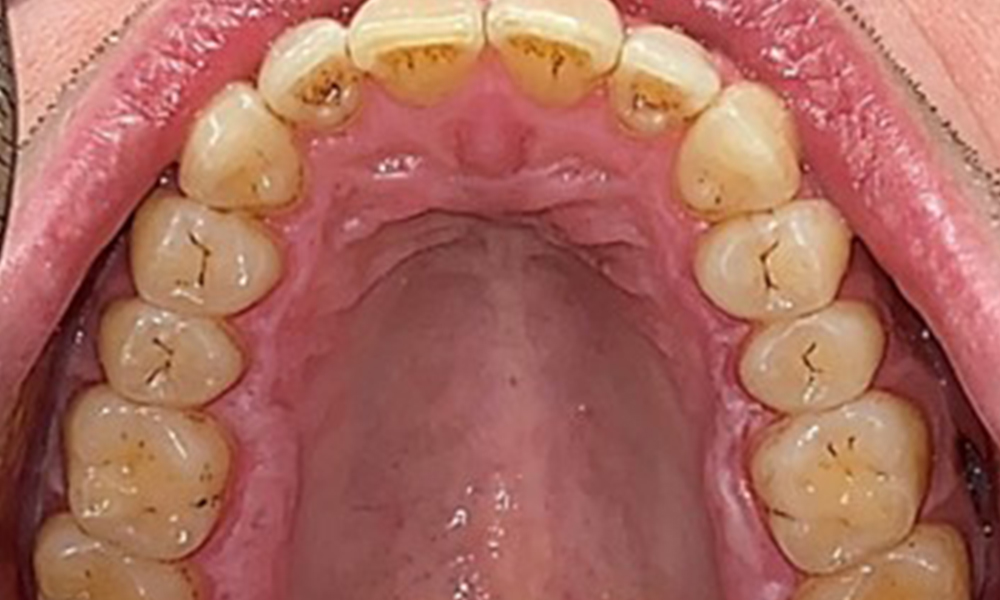

Occlusal view of the mandible, © Dr R. Krapf

Fig. 4: Occlusal view of the mandible, © Dr R. Krapf

There were no pathological extraoral findings. During intraoral examination, inspection of the frontal view revealed brownish discolouration near the keratinised gingiva and at the transition to the moveable mucosa (Fig. 2), which could be attributed to nicotine consumption. Whitish mucosal lesions were observed on the palate, particularly near the maxillary molar palatal surfaces, indicating increased keratinisation and can also be attributed to nicotine consumption. The tongue was covered with a removable white and brownish coating.

The patient has full dentition with a total of 28 teeth. There were noteworthy erosions and attritions. (Fig. 4, Fig. 5). Due to bruxism, the patient has been wearing a splint with an adjusted bite block at night for many years. The erosions were caused by long-term consumption of isotonic beverages. No periodontal bone loss or active caries were observed.